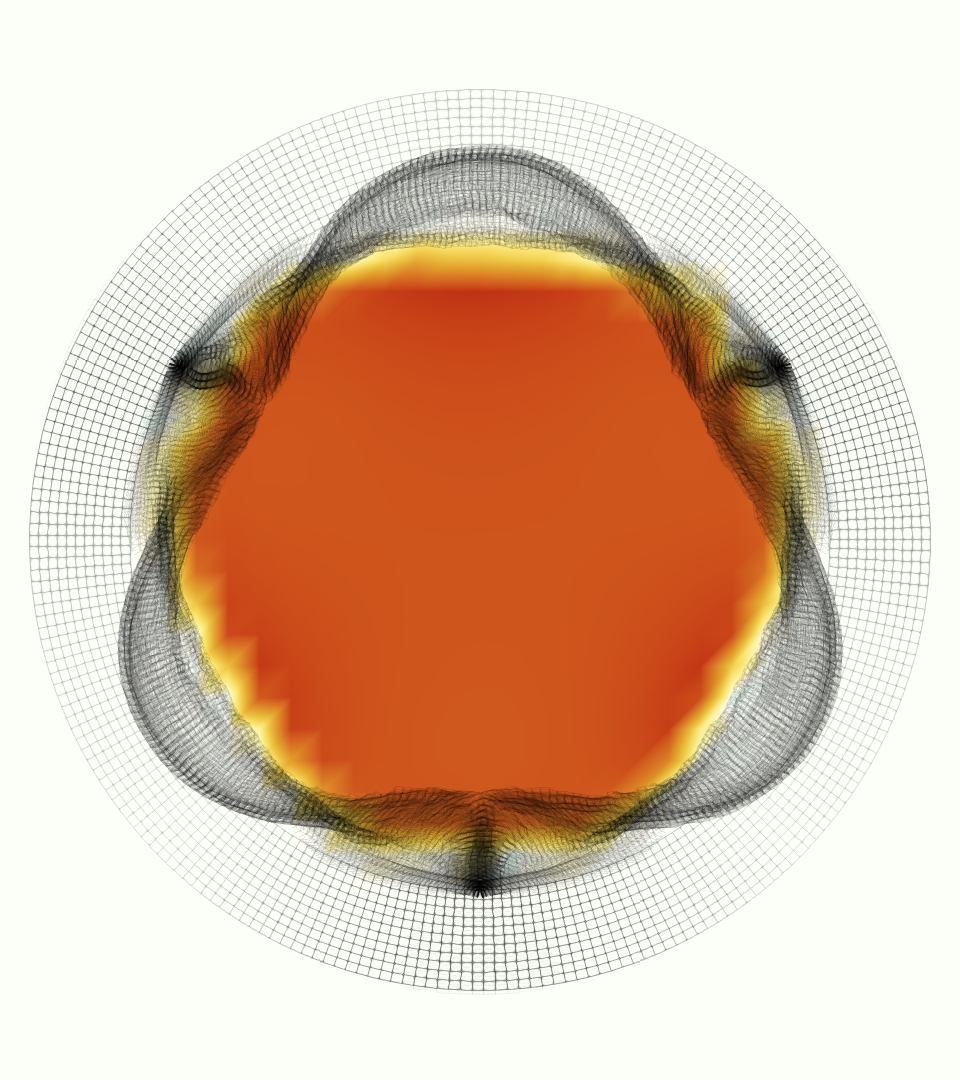

At = 0, the axial slice directly at the valve annulus shown in columns 1 and 2 in Figure 6, there was excellent agreement between the simulation and experiment over the cardiac cycle in the speed and shape of the jet through the valve. In both cases, the axial velocity increased as the flow accelerated during systole and the valve leaflets opened, then decreased during diastole with slight negative velocity before the valve leaflets were fully closed. The forward flow through the valve annulus did not form a full circle, but rather developed a triangular shape with a point of the triangle forming along the interior curve of the vessel, at the bottom of the axial slices. At = 0, the points of this triangular jet shape aligned with the commissures of the valve. This shape persisted during peak systole and was well-matched by the simulation.

The axial slice = 0.625 cm, shown in columns 3 and 4 in Figure 6, cut through the support scaffolding of the valve and the leaflets when they are open. In the experimental data, the shape of the jet changed as it moved downstream. A triangular shape occurred, but the points were then aligned with the middle of each open leaflet as opposed to the commissures. Those points were also more rounded than they were at = 0. The peak velocity of the jet was faster at = 0.625 cm than at = 0, as the flow accelerated through the open valve leaflets. The simulation produced these features at = 0.625 cm. The triangular shape of the jet shifted similarly, and its speed increased compared to the upstream slice. As the flow decelerated into diastole, the jet shape remained roughly triangular but diminished in intensity before disappearing after valve closure.

The jet continued to develop at = 1.25 cm, an axial slice immediately downstream of the valve scaffolding and open leaflets, shown in columns 5 and 6 in Figure 6. In the experimental data, the points of the triangular jet shape extended further towards the vessel wall. In addition, regions of reversed flow developed in the locations downstream of the commissures, resulting in curved sides to the shape of the jet. Each tip of the jet was unique, due to variations in the individual leaflets in the physical bioprosthetic valve. These variations are apparent in the velocity fields, possibly because the jet edges are similar enough cycle to cycle that irregularities are still being captured even with phase averaging. Further discussion of these features can be found in Schiavone et al. [39], which showed that the jet tip shapes occurred in different pulmonary anatomies, demonstrating that they were likely due to inherent properties of each leaflet. The leaflets in the mathematical model of the valve are identical, so these nuances in leaflet variation could not be replicated. The simulation did capture some of the extension of the tips of the jet, as they were closer to vessel wall at slice = 1.25 cm than = 0.625 cm. The curves in the triangular sides of the jet were also present in the simulation, though they were less pronounced than the experimental data. At both = 0.625 cm and = 1.25 cm, the jet shape in the simulation was smoother than the jet in experiment. It is possible that the free edges of the leaflets in the mathematical model are not fully replicating the behavior of the physical leaflets of the bioprosthetic valve, in particular the amplitude or frequency of leaflet flutter, leading to the variations seen in the jet shape at = 1.25 cm downstream of the leaflet edges. The simulation, however, does capture the key features of the triangular shape and speed of the jet. Overall, qualitative comparisons demonstrated that the simulation reproduced key features of the flow during systole and diastole.

The phase-averaged, resampled velocity fields during peak systole and flow rates at each resolution are shown in Figure 10. Despite the limitations discussed above, we observe similar qualitative trends in the flow field at all resolutions. At all resolutions, a jet formed and angled up downstream of the valve orifice, as shown in the sagittal view. The jets showed a triangle-like cross section at with points aligned with the commissures. At cm, the jet appears like a rounded triangle in the opposing orientation, with its points aligned with the center of the leaflets. At cm, the jet is narrower downstream of the commissures, and wider downstream of the leaflets, again with a triangle-like cross section. The area of the jet increased with resolution, as expected given the IB method thickening of the valve structure. The narrowed jets at the two more coarse resolutions show locally elevated velocities relative to the two more fine resolutions. Figure 11 shows the instantaneous velocity fields at each resolution in the same axial and sagittal views. At 0.9 mm, the sagittal view shows a qualitatively different jet than at finer resolutions, with regions of lower velocity farther from the vessel wall, indicating insufficient resolution. At 0.9 and 0.68 mm, the jet is visibly narrowed compared to higher resolutions. While some features are similar at these two coarse resolutions, we conclude that the narrower jets indicate these simulations are under-resolved. Flows in the three finest resolutions, 0.45, 0.34 and 0.28 mm. appeared qualitatively similar, with slightly more fine structure detail in both the axial and sagittal views present at the edges of the jet. The jets in the axial views all showed a similar triangle-like cross section, slightly narrower downstream of the commissures, as in the phase-averaged fields. In both the phase-averaged and instantaneous fields, the three finest resolutions appear sufficiently similar that the conclusions of this study would be identical with any of these resolutions.